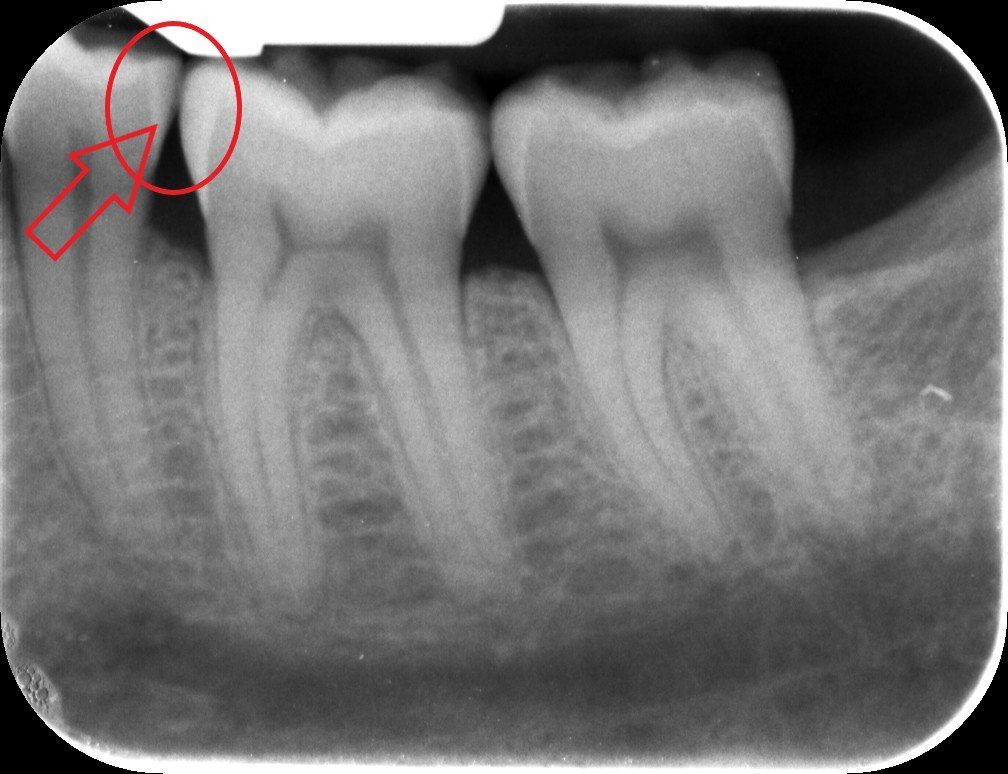

Viene presentato un caso in cui si evidenzia la presenza di carie mesiale e distale su un 25 (secondo premolare superiore di destra) attraverso l'analisi radiografica. Si deve sottolineare la difficoltà di metterne in risalto e di determinarne l'estensione solo mediante la radiografia. Nella fotografia successiva, l'entità e l'estensione della carie appaiono notevolmente superiori a quanto potesse essere dedotto dalla sola radiografia. Si mostra poi la cavità ripulita dalla carie, evidenziando la perdita di tessuto dentale causata da essa. Infine, si presenta l'otturazione appena completata, con i segni della cartina da articolazione ancora visibili, utilizzata per verificare l'altezza della cura, che richiederà successivamente un ulteriore rifinitura e lucidatura.

Un particolare utilizzo di due fasci laser e di un sensore che trasforma la transilluminazione in immagine visibile sul monitor del computer trova un utilizzo anche nella diagnosi della carie qualora l’immagine radiografica risulti dubbia o non dirimente di lesione cariosa. Ecco un esempio in cui radiologicamente si vede un’immagine non chiaramente rapportabile ad una carie come indicato dalle frecce nella radiografia a fianco. Con l’ausilio del laser si riesce ad evidenziarne completamente i limiti e la grandezza come visibile dalle due immagini e dalle frecce che indicano la carie. Tuttavia, per correttezza, va spiegato che l’efficacia di questa indagine può essere effettuata solo in determinate circostanze cliniche e che le radiografie risultano sempre necessarie.